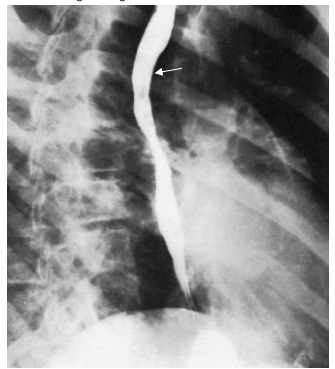

Observe a imagem a seguir.

A seta indica

Provas